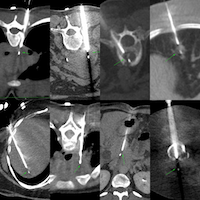

I discuss the how, where, when and why of CT guided spine biopsies.

Lecture: Spine Biopsies - Tips and Tricks

Spine biopsies are simple, but need a little planning to arrive at the right approach to safely get as much material as possible for the diagnosis.